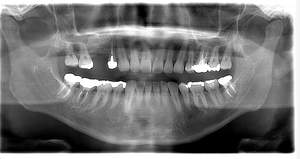

レントゲン写真

- 透過像

| 年齢 | 50代・男性 |

| 主訴 | 右下歯が疼く |

| 治療内容 | ・右下6番インプラント ※1:FGG(遊離歯肉移植術)とは、足りない歯ぐきを上顎から上皮を切り取り移植する外科手術 |

| 治療費 | 合計:902,000円(税込) ■内訳 |

| 治療期間 | 9ヵ月 |

| 治療方針 | 右下の当該歯は歯根破折により保存不可能と診断しました。歯周疾患も伴っていたため抜歯後に骨吸収※1が大きく起こることが予測できました。チタンメッシュ併用骨再生誘導法(GBR※2)を選択しインプラント埋入と同時に行い自然な歯槽骨のラインを再現しました。またGBRを行う際にインプラント辺縁の付着歯肉の減少が起こる為、遊離歯肉移植術(FGG※3)を行い清掃性を考慮した形態に仕上げました。 ■治療方針の解説 治療した右下の歯をレントゲンで撮影したところ根本の部分に黒く写る箇所があり「根尖性慢性周囲炎※1」と診断。また歯周病も進行していました。 ※1 骨吸収・・・歯槽骨という歯を支える骨がなくなっていくこと |

| 担当者所見 | 主訴の右下だけでなく歯茎の腫れ、発赤があり不良補綴や不良充填など他にも治療箇所が多数ありました。プラークコントロールが不良であった為まずはブラッシング指導を行いセルフケアの重要性を理解していただくところからスタートしました。 右下6番の歯はインプラント治療を行なった結果審美的にも機能的にも患者様の満足を得ることができました。骨造成と歯肉移植も行なった為インプラントを支える十分な歯周組織の獲得ができたと思っております。 |